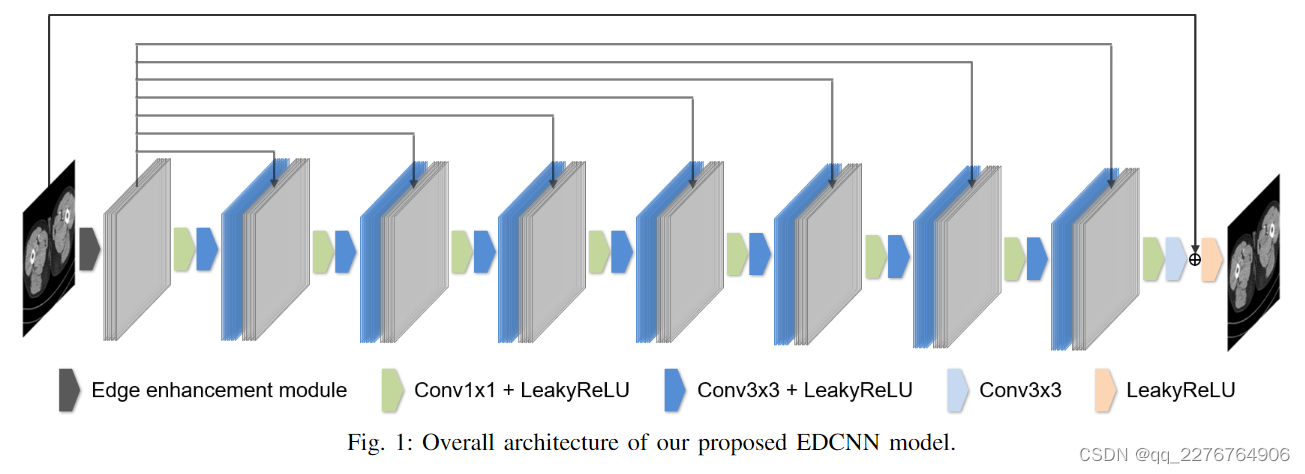

所提出的网络架构如图1所示,称为基于边缘增强的密集连接卷积神经网络(EDCNN)。 整个模型由一个边缘增强模块和八个卷积块组成。 边缘增强模块已在上一节中进行了解释。 我们使用的可训练 Sobel 算子数量为 32 个(四种类型共各8 组)。

对于边缘增强模块之后的模型结构,我们设计的目的是尽可能保留过程中的图像细节。 受DenseNet[26]的启发,我们设计了一种密集连接的低剂量CT去噪模型,试图充分利用提取的边缘信息和原始输入。 具体来说,如图1中的线所示,我们通过跳跃连接将边缘增强模块的输出传递给每个卷积块,并在通道维度上将它们连接起来。 除了最后一层之外,后面的卷积块的内部结构完全相同。 这些块由1x1和3x3卷积组成,卷积滤波器的数量全部设置为32。最后一层3x3卷积滤波器的数量为1,对应于单个通道的输出。 在每个块中,具有 1x1 内核的逐点卷积用于融合前一层和边缘增强模块的输出,而具有 3x3 内核的卷积则用于像往常一样学习图像中的特征。 此外,为了保持输出大小和输入大小相同,对模型中的特征图进行填充,以确保在前向传播过程中空间大小不会改变。 为了加速模型的收敛并简化模型主体结构的任务,我们让模型直接学习噪声分布和重构信息。 因此最后一个卷积块的输出与原始低剂量CT图像相加,得到最终的噪声去噪图像。 在图 1 中,顶线代表这种残差连接,由圆圈和加号组成的符号代表逐元素加法。